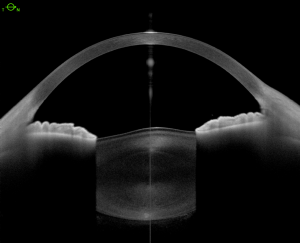

Anterior lenticonus

The defective IV-collagen induces thinning and fragility of the lens capsule resulting in lenticonus. Several studies have demonstrated changes by electron microscopy as multiple linear dehiscences in the inner 2/3 of the capsule, containing fibrillar material and vacuoles. In addition to the histological change of the anterior capsule, the weakened structure is stressed during accommodation, as the anterior lens curvature becomes more convex centrally, rarely resulting in capsular rupture.[17] Posterior lenticonus may also occur but is less common.[4]

- Anterior lenticonus with “oil droplet” sign and usually axial, 2–7 mm.[8]

Cataract surgery with intraocular lens implantation results in successful visual recovery. During surgery, centrally protruded fragile lens capsule must be meticulously handled to create a well-centered continuous curvilinear capsulorhexis. Femtosecond laser-assisted capsulorhexis has been shown to be a safe procedure in these patients.[20] Cataract surgery can be successful even in the presence of a spontaneously ruptured capsule before surgery.[21] Recent evidence suggests that cataract surgery, however, may predispose to early development of a macular hole [16]